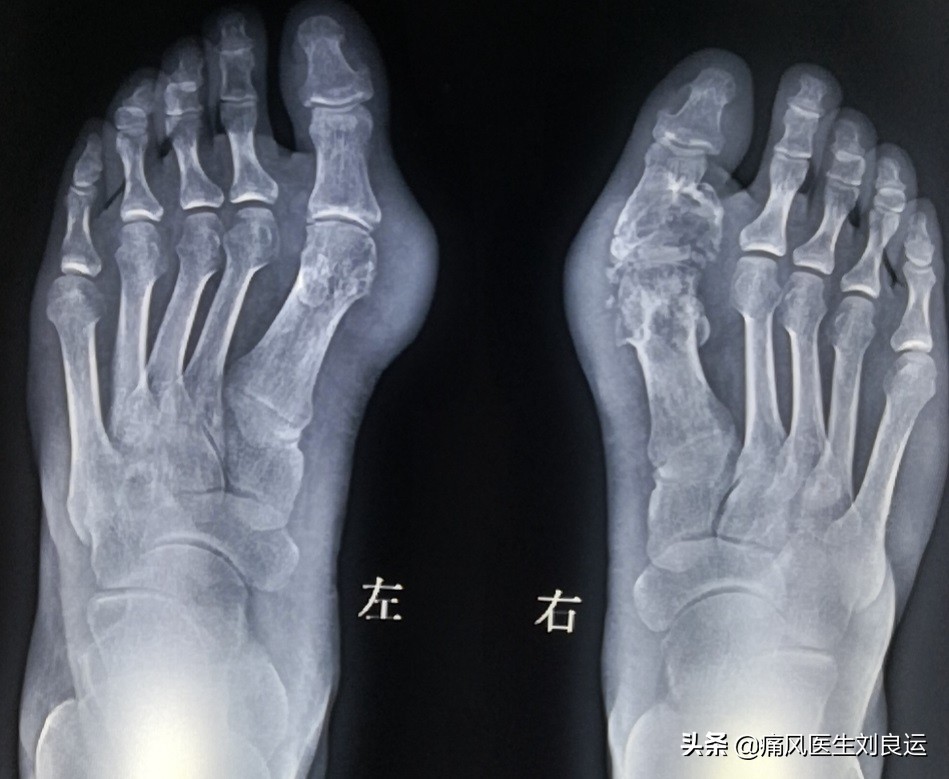

DR下足部痛风症状,大脚趾明显肿大、骨质受损、尿酸盐结晶沉积